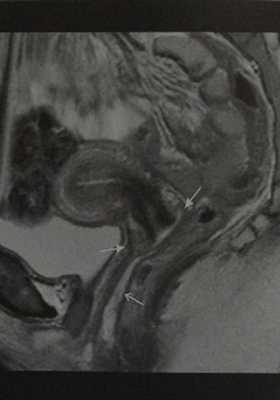

Влагалище женщины 30 лет в первой фазе менструального цикла. Сагиттальное Т2-взвешенное изображение. Зональная анатомия: гиперинтенсивная околовлагалищная клетчатка (стрелка с открытым наконечником), гипоинтенсивный мышечный слой и внутренний слой гиперинтенсивной слизистой оболочки. Верхняя треть влагалища: передний и задний своды (стрелки).